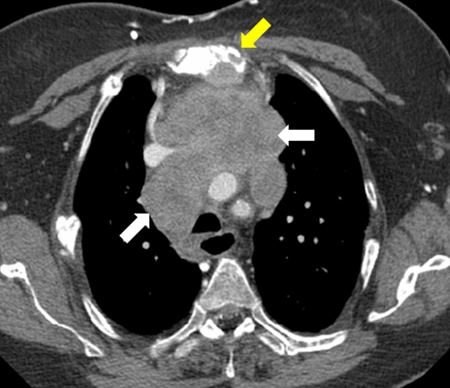

Imagem por tomografia computadorizada (TC) de grande carcinoma tímico (seta branca) com invasão esternal (seta amarela)

Dos acervos do Dr. Mario Gasparri e do Dr. Nicholas Choong